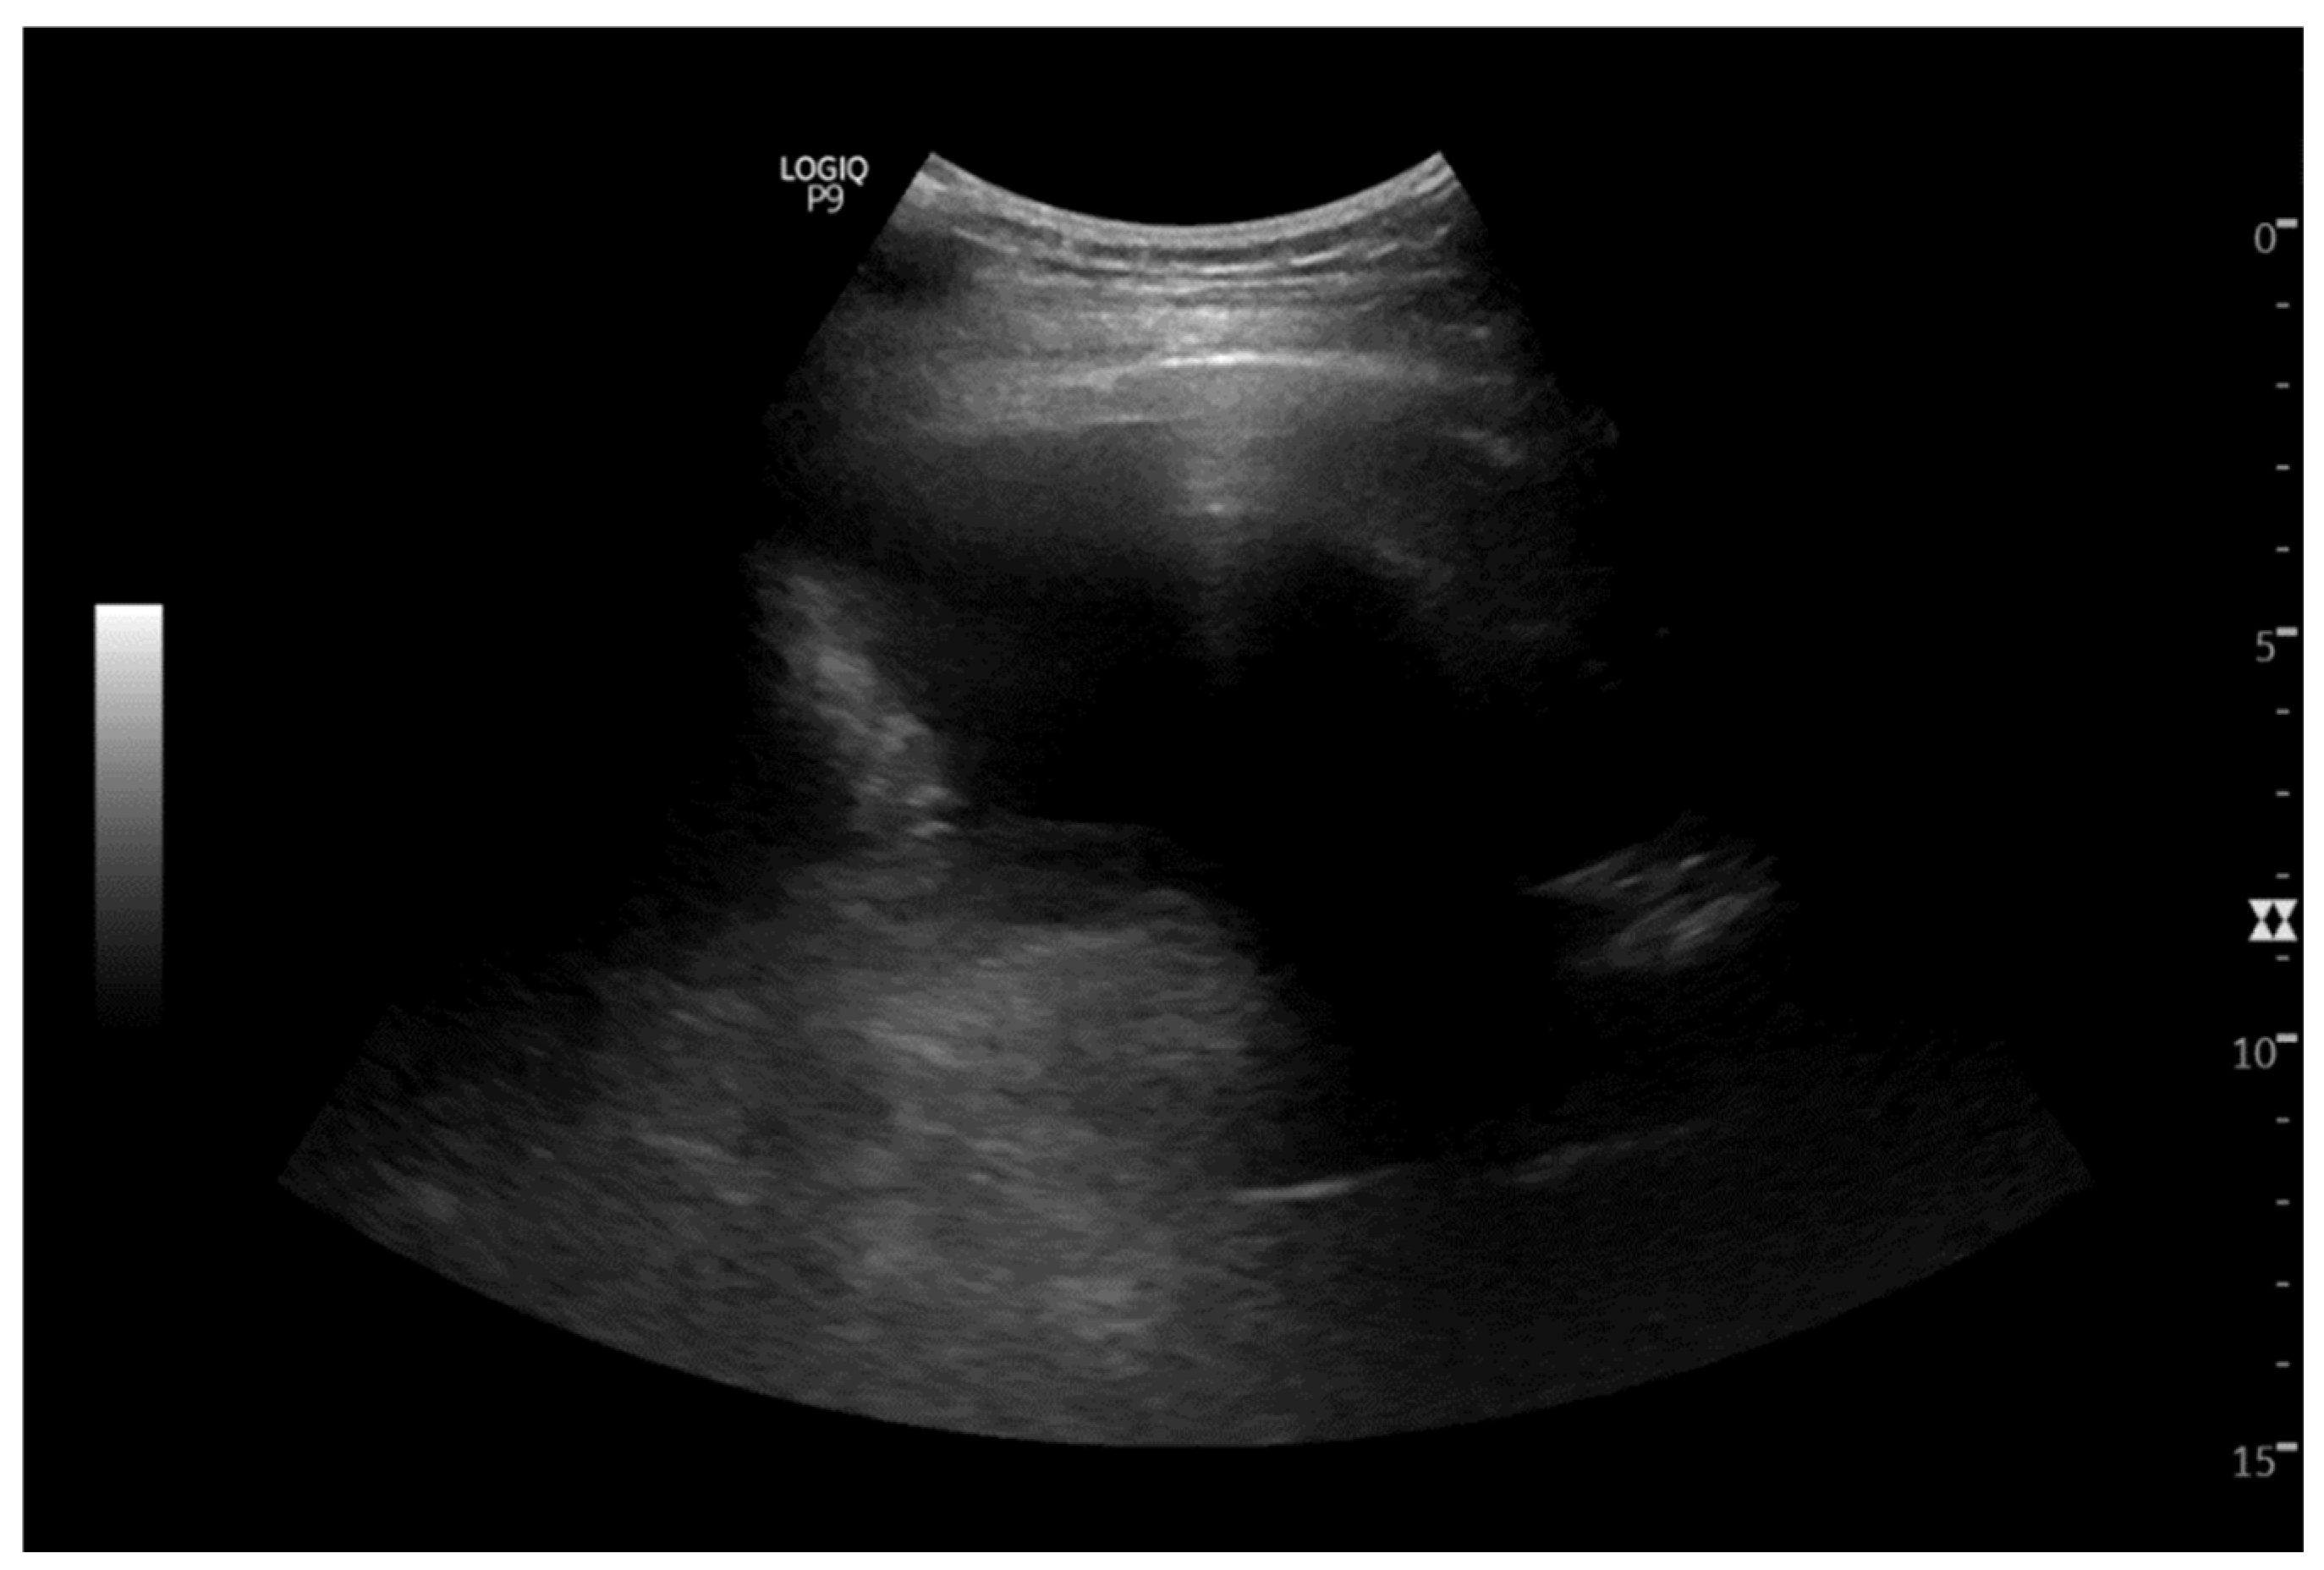

2. Case Report